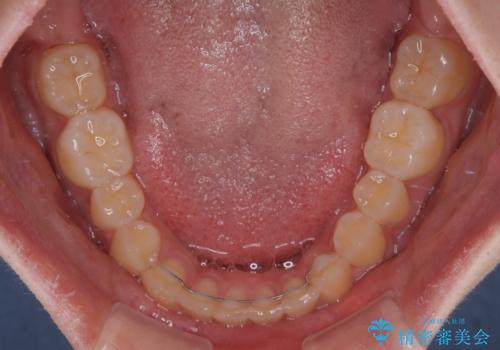

- 上顎前歯の隙間を気にして来院された患者様です。

目立たない装置を希望とのことで、インビザラインを用いて矯正治療を行うこととしました。

一度インビザラインのマウスピースセットをお渡しすると1年以上来院されず、マウスピースを破損したり紛失したりすると来院されるというのんびりとしたペースで治療を行ったため、4年間という長期にわたる治療となりました。

最終的には隙間は全て閉じ、綺麗な仕上がりとなりました。